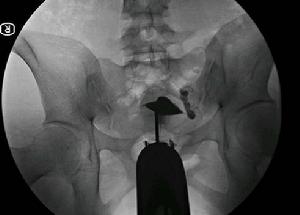

宮腔鏡輸卵管損傷示意圖(一)婦產科手術

據輸卵管手術損傷統計以婦科手術最為多,占輸卵管手損傷的82%,其中又以子宮切除最多,占輸卵管手術損傷65.7%。損傷部位以盆段輸卵管居多,其中尤以子宮動脈與輸卵管交叉處損傷率最高,在較少的情況下如子宮陰道切除術、子宮破裂或剖腹產行子宮切除術、卵巢惡性腫瘤或較大的卵巢囊腫切除術、子宮懸吊術膀胱陰道瘺修補術等,也易發生輸卵管損傷。